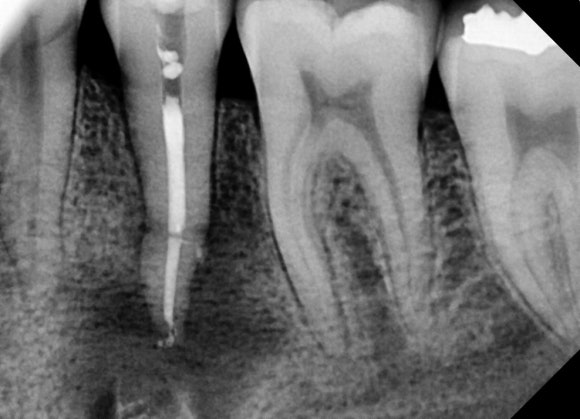

신경치료 마무리, 레진으로 구멍 매꾸기

![[치외치신경치료] 뿌리 끝 염증이 커서 발치해야된대요! 치아 머리에 볼~록! 알고보면 무서운 작은 혹 (서울재생치과) 관련 이미지 21](https://pub-9f2bb3498faf4d1d8714b41df24753e3.r2.dev/content/clinics/archive/nqmm0udu86/naver_blog/honeybeevuvu/assets/by_hash/1ae04054a21cf0510f43e67a36f4d45f3e77db7ec9a2c69c395cae91bb540e22.jpg)

깨끗하게 신경치료를 마무리합니다.

신경치료를 마무리한다는 것은,

신경치료용 특수 약제를

뿌리 속 빈공간에 넣어 밀봉해주는 것을

뜻합니다.

![[치외치신경치료] 뿌리 끝 염증이 커서 발치해야된대요! 치아 머리에 볼~록! 알고보면 무서운 작은 혹 (서울재생치과) 관련 이미지 22](https://pub-9f2bb3498faf4d1d8714b41df24753e3.r2.dev/content/clinics/archive/nqmm0udu86/naver_blog/honeybeevuvu/assets/by_hash/4b753b7f538ee048c5a3bcbf74e6ac9f2543409db0f41284be473927cee246e4.jpg)

뿌리 끝까지 깨끗하게 밀봉되었습니다.